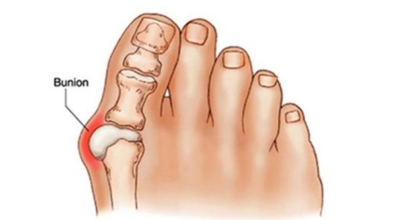

엄지발가락이 두번째 발가락 쪽으로 과도하게 휘고 엄지발가락과 관절을 이루는 중족골은 반대로 안쪽으로 치우치는 변형 되며 발가락이 발등 쪽으로 휘거나 회전(엄지발가락 축을 중점으로 내측으로 회전; 회내)하는 변형을 동반한 삼차원적인 변형을 말합니다.

육안상으로 확연하게 엄지발가락 과 같은 변형 보이며 초기에는 굳은살도 관찰되고 약간의 통증도 있습니다. 엄지발가락 돌출 부위의 통증으로 이 부위가 신발에 자극을 받아 두꺼워지고 염증이 생겨 통증이 발생합니다. 휘어지지 않은 발바닥에 굳은살로 인해 정상 보행이 어렵고 심한 경우 통증으로 인하여 신발 착용은 물론 정상 보행도 어려워집니다. 연속적으로 증상이 악화되면 엄지발가락이 겹쳐지거나 탈구 될 수도 있습니다.